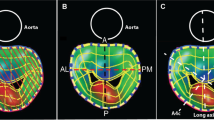

3D direct planimetry of MVA was determined through an en-face view of the mitral valve in a method similar to 2D echocardiography of the left atrial aspect (MVALA) and left ventricular aspect (MVALV) on the echocardiographic machine. First, the maximum early diastolic opening of the mitral valve orifice was chosen which is the same frame as used for the MPR method. Then, we performed manual rotation of the 3D image to ascertain that the mitral valve orifice was parallel to the screen when the MVA was highest (Fig. 3). The planimetry MVA measurement was obtained from the magnified view (Fig. 4). Additionally, two orthogonal diameters, the major and the minor diameter of the mitral valve orifice, were measured from the left atrial aspect (MajorLA, MinorLA) and left ventricular aspect (MajorLV, MinorLV) (Fig. 4).

In order to test the reliability of the 3D direct planimetry measurement, we used the face-cropping function built into the machine, which can cut 3D images in a plane parallel to the screen. After the 3D direct measurement method was completed, the face-cropping function was used on the same 3D image to adjust the orientation of the 3D image for layer-by-layer cutting, so that the cutting plane could cut both commissures simultaneously, as well as the A2 and P2 segments. In that situation, the mitral valve orifice is considered to be parallel to the screen, resulting in a true-sized orifice that can be measured by 3D direct planimetry (MVALA FACE and MVALV FACE) (Fig. 5).

A mitral valve orifice parallel to the screen as judged by the face-cropping method. a 3D zoom image of a mitral valve orifice from the left ventricular perspective. *A2, P2 scallops and commissures. b Cutting plane cut A2 and P2 scallops simultaneously. c Cutting plane cut both commissures simultaneously